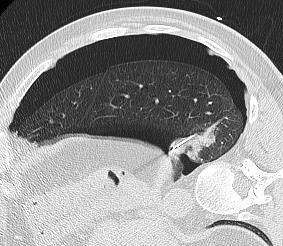

| 下肺消融的技术 包括病人位置、消融方式的选择、入路选择等 病例1:男 66岁 甲状腺癌肺转移,建议热消融

病例3: 下叶的结节是可移动的,变化体位后可以出现在的位置

病人治疗时的位置非常关键 - 病人的位置应该让入路更加便利 - 正确地看见病变 - 入针轨迹短 病例4: